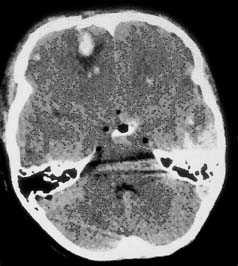

Компьютерная томография при травматическом повреждении головного мозга.

Применение компьютерной томографии в нейротравматологии существенно изменило представление о возможностях диагностики различных черепно-мозговых повреждений. КТ является в настоящий момент «золотым стандартом» - наиболее информативным методом обследования больных с черепно-мозговыми травмами и позволяет в самые короткие сроки судить о механизмах возникновения поражения мозга, его характере, распространенности, выраженности отека и дислокации мозга, а также динамике этих изменений.

КТ позволяет последовательно изучить мягкие ткани головы, кости черепа, вещество мозга, эпидуральные, субдуральные, субарахноидальные пространства, цистерны основания и желудочки мозга:

- выявить переломы свода и основания черепа (с чувствительностью, намного превышающей традиционную рентгенографию) ,

- выявить наличие внутричерепной гематомы (её характер, локализацию, размеры),

- выявить наличие очага ушиба головного мозга (его локализацию, размеры, характер, наличие геморрагического компонента),

- определить степень сдавления или дислокации головного мозга объемным процессом,

- выявить наличие диффузного или перифокального отека и его степени,

- выявить субарахноидальное кровоизлияние,

- выявить внутрижелудочковую гематому,

- выявить наличие пневмоцефалии.

Методом выбора при диагностике ушиба головного мозга является КТ головного мозга. На КТ определяют ограниченную зону пониженной плотности, возможны переломы костей свода черепа, субарахноидальное кровоизлияние. При ушибе мозга средней степени тяжести на КТ или спиральной КТ в большинстве случаев выявляют очаговые изменения (некомпактно расположенные зоны пониженной плотности с небольшими участками повышенной плотности).

При ушибе тяжелой степени на КТ определяются зоны неоднородного повышения плотности (чередование участков повышенной и пониженной плотности). Перифокальный отек головного мозга сильно выражен. Формируется гиподенсивная дорожка в область ближайшего отдела бокового желудочка. Через нее происходит сброс жидкости с продуктами распада крови и мозговой ткани.

КТ-картина диффузного аксонального поражения мозга характеризуется увеличением объема мозга, в результате которого под сдавлением находятся боковые и III желудочки, субарахноидальные конвекситальные пространства, а также цистерны основания мозга. Нередко выявляют наличие мелкоочаговых геморрагий в белом веществе полушарий мозга, мозолистом теле, подкорковых и стволовых структурах.

На КТ определяют двояковыпуклую, реже плоско-выпуклую ограниченною зону повышенной плотности, которая примыкает к своду черепа и локализируется в пределах одной или двух долей. Однако, если источников кровотечения несколько, зона повышенной плотности может быть значительного размера и иметь серповидной форму.